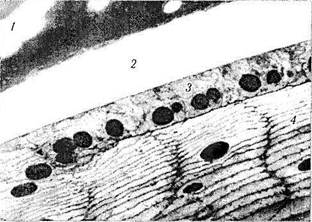

В световом микроскопе капсула выглядит прозрачной, гомогенной (рис. 3.4.8). В поляризованном свете выявляется ее пластинчатая волокнистая структура. При этом волокнистость располагается параллельно поверхности хрусталика [203, 420]. Капсула также положительно окрашивается при проведении ШИК-реакции, что свидетельствует о наличии в ее составе большого количества протеогликанов [798].

Рис. 3.4.8. Светооптическое строение капсулы хрусталика, эпителия капсулы хрусталика и хрусталиковых волокон наружных слоев:

/ — капсула хрусталика; 2 — эпителиальный слой капсулы хрусталика; 3 — хрусталиковые волокна

Ультраструктурно капсула имеет относительно аморфное строение (рис. 3.4.6, 3.4.9). Незначительная пластинчатость намечается благодаря рассеиванию электронов нитевидными элементами, складывающимися в пластины.

Выявляется около 40 пластин, толщина каждой из которых равна приблизительно 40 нм [1197]. При большем увеличении микроскопа выявляются нежные коллагеновые фибриллы диаметром 2,5 нм [798].

Рис. 3.4.9. Ультраструктура цинновой связки, капсулы хрусталика, эпителия капсулы хрусталика и хрусталиковых волокон наружных слоев:

/ — циннова связка; 2 — капсула хрусталика; 3 — эпителиальный слой капсулы хрусталика; 4 — хрусталиковые волокна